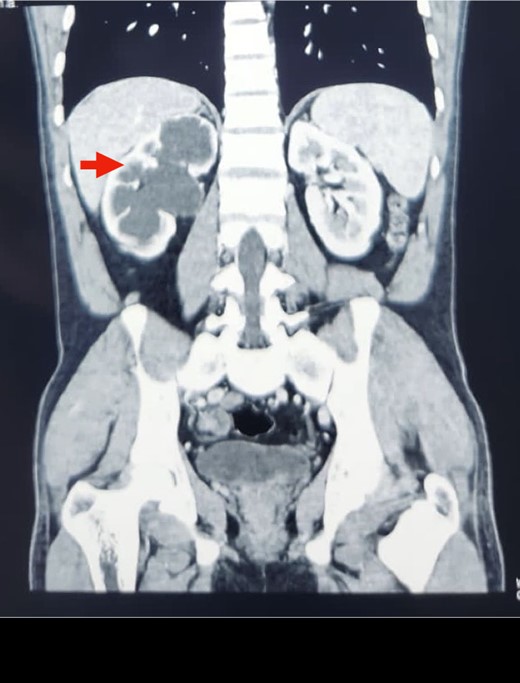

A midline incision was given, and the abdomen was opened from 4 cm below the xiphisternum to 3 cm above the pubic symphysis. The ascending colon along with the hepatic flexure was completely mobilized medially to expose the retroperitoneum. Careful dissection was done to identify the IVC and its the relations to the right ureter. The proximal dilated ureter and right pelvicalyceal system were identified, and dissection was continued laterally. The ureter was traced and noticed to course behind the IVC at the level of the L2–L3 vertebra, exiting to lie medially in the groove between the IVC and the aorta (Fig. 3). The ureter was divided proximal to the point where it coursed behind the IVC until it came out medial to IVC (Fig. 4). The retrocaval segment was brought anteriorly, resected from the normal distal ureter, and ureteropelvic anastomosis was done using 3–0 Polyglactin sutures lateral to the IVC (Fig. 5). This procedure eliminated the compression on the ureter. An abdominal drain was placed.

Intraoperative image showing the course of the retrocaval ureter and the important structures around it.